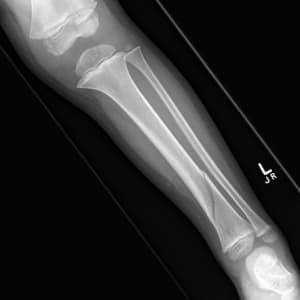

На изображении представлены берцовые кости человека.

Травмы берцовых костей могут включать переломы, вывихи и повреждения связок. Переломы могут произойти в результате падений, спортивных травм или аварий. Вывихи могут возникнуть при резких движениях или неправильной нагрузке на суставы. Важно своевременно обращаться за медицинской помощью при подозрении на травму, чтобы избежать осложнений и обеспечить правильное лечение.